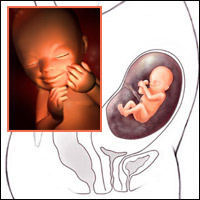

Thai nhi 19 tuần

Thai nhi tuần thứ 19 đã có thể nghe được âm thanh từ bên ngoài bụng mẹ.

Tuần 19: Mít yêu đã bằng quả xoài